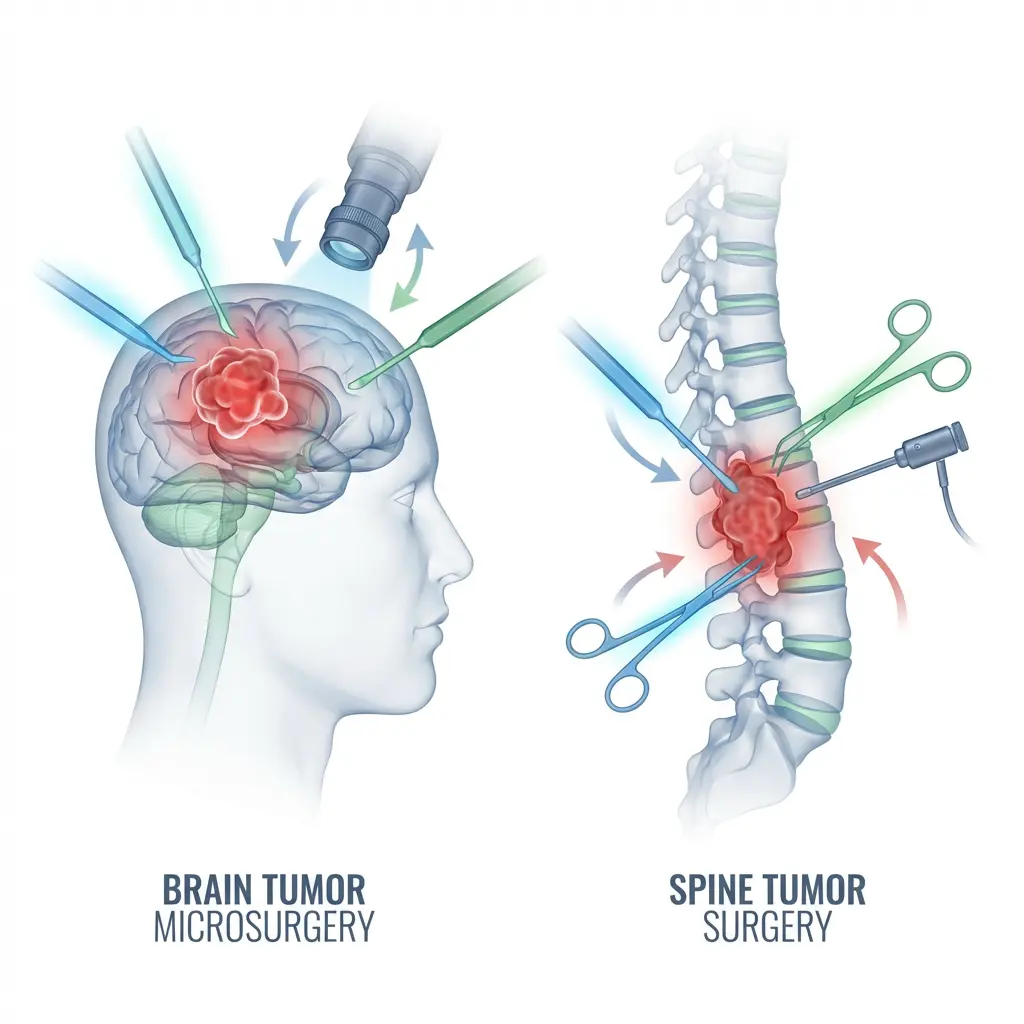

Advanced Neurosurgery & Brain Care

We offer a comprehensive range of advanced neurosurgical treatments for brain, spine, and neurological conditions under the guidance of the best neurosurgeon in Ahmedabad. Each service is designed to provide precise diagnosis, effective treatment, and long-term patient care.

Dr Chirag Solanki, the best Neurosurgeon in Gujarat as expertise in treating a wide range of neurological conditions, including brain strokes, aneurysms, brain tumors, Parkinson’s disease, tremors, dystonia, epilepsy, pain, incontinence, psychosurgeries, spine problems and spinal tumors and traumatic brain injuries. We also offer comprehensive care options, from minimally invasive procedures to complex surgical interventions.